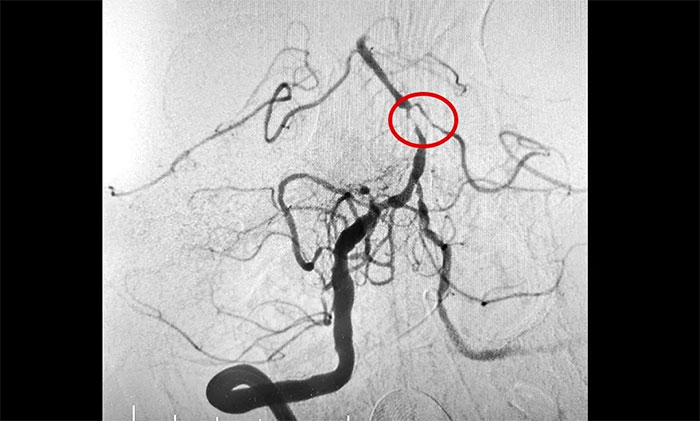

磁共振检查提示,脑干梗塞软化灶形成;双侧大脑半球白质多发腔梗;脑动脉硬化,左侧大脑后动脉纤细远端未见显影,右侧大脑后动脉P1段狭窄,左侧椎动脉纤细。DSA提示左侧基底动脉中段次全闭塞,右椎动脉V4段轻度狭窄,左椎动脉V4末段重度狭窄,左小脑前下动脉起始段重度狭窄,右小脑后下动脉起始段重度狭窄,双侧大脑后动脉多发狭窄。

席刚明教授充分评估患者的病情及血管情况,本例患者为基底动脉主干病变,呈现为“一线天”样狭窄,考虑基底动脉重度狭窄为患者再次脑缺血发作的根源,狭窄处随时可能形成血栓引发血管急性闭塞。一旦闭塞,患者将可能出现深昏迷、四肢瘫痪,甚至危及生命,可以说是“命悬一线”,即使侥幸保住性命,大概率也会成为植物状态或遗留其他严重残障。

▲ 左侧基底动脉中段次全闭塞